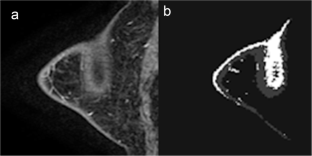

Fig. 2